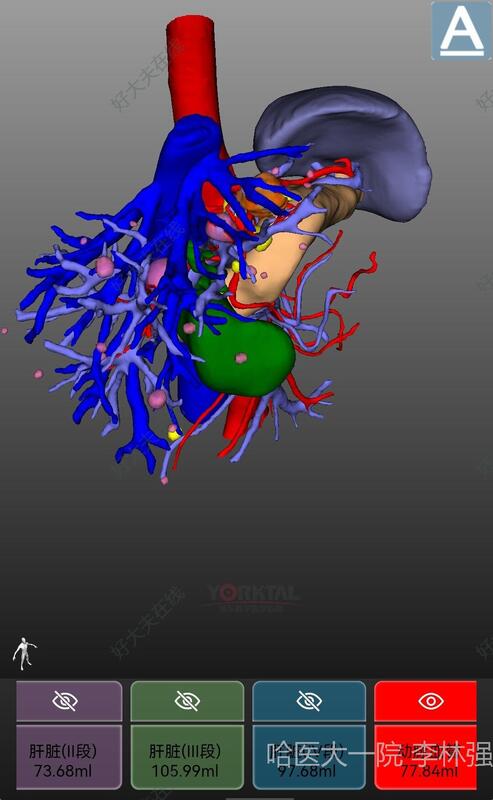

李林强

哈医大一院

肝脏微创外科

机器人微创切除肝癌

患者既往乙肝,肝硬化,发现肝左外叶肿瘤,直径约2cm,AFP显著升高

机器人辅助下肝左外叶切除术